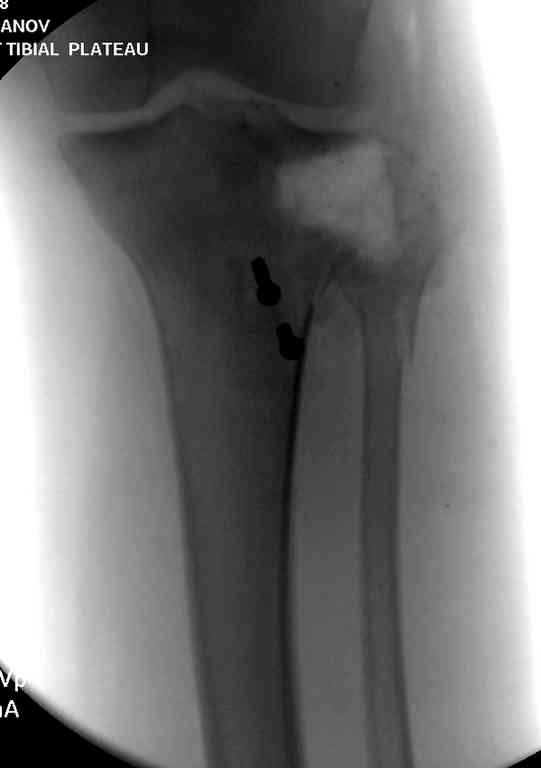

На вашем снимке из-за ротации трудно угадать положение пластины, и желательно сделать снимок с захватом верхнего участка бедра.

Одинокий кортикальный шуруп не удержит тибиальный бугор, сустав тибиал плато оставлен без репозиции и фиксации.

Пожалуйста, снимки.

Коллеги фиксатор Numelock II